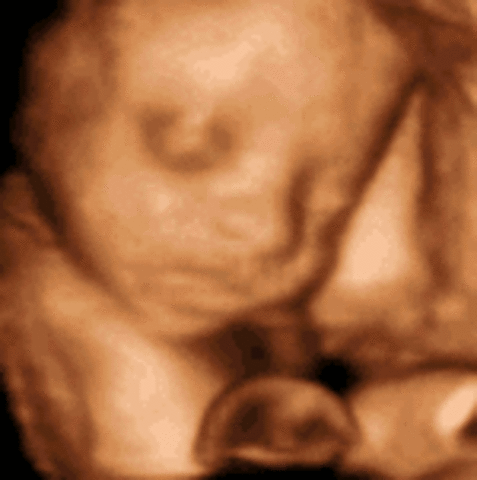

• Week 26: Second Trimester Ends This Week

The fetus' hands are moving a lot more and its eyes are beginning to open. The baby also weighs about 1.7 pounds at this stage. To calm itself down, the baby will suck its thumb.

• Week 27: Eyes Can Open

Week 27: Eyes Can Open

This is the start of the third trimester and the baby now looks almost exactly how it will when it is born. The eyes can now fully blink.